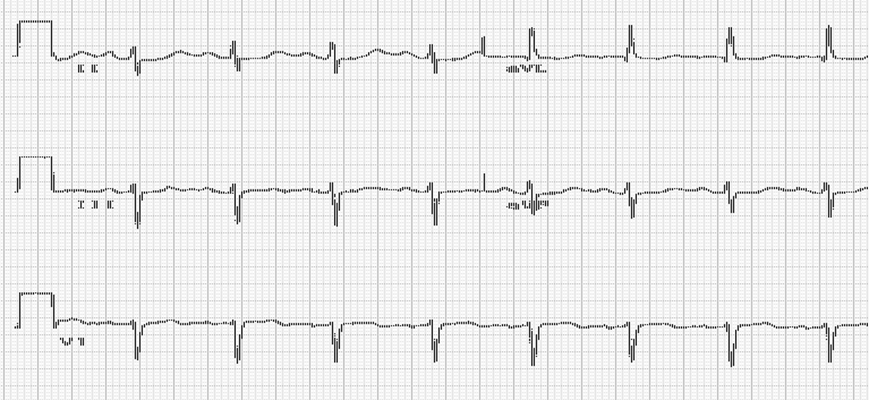

預激綜合徵心電圖 (9)

預激綜合徵心電圖 (90)

預激綜合徵心電圖 (91)

預激綜合徵心電圖 (92)

預激綜合徵心電圖 (93)

預激綜合徵心電圖 (94)

預激綜合徵心電圖 (95)

預激綜合徵心電圖 (96)